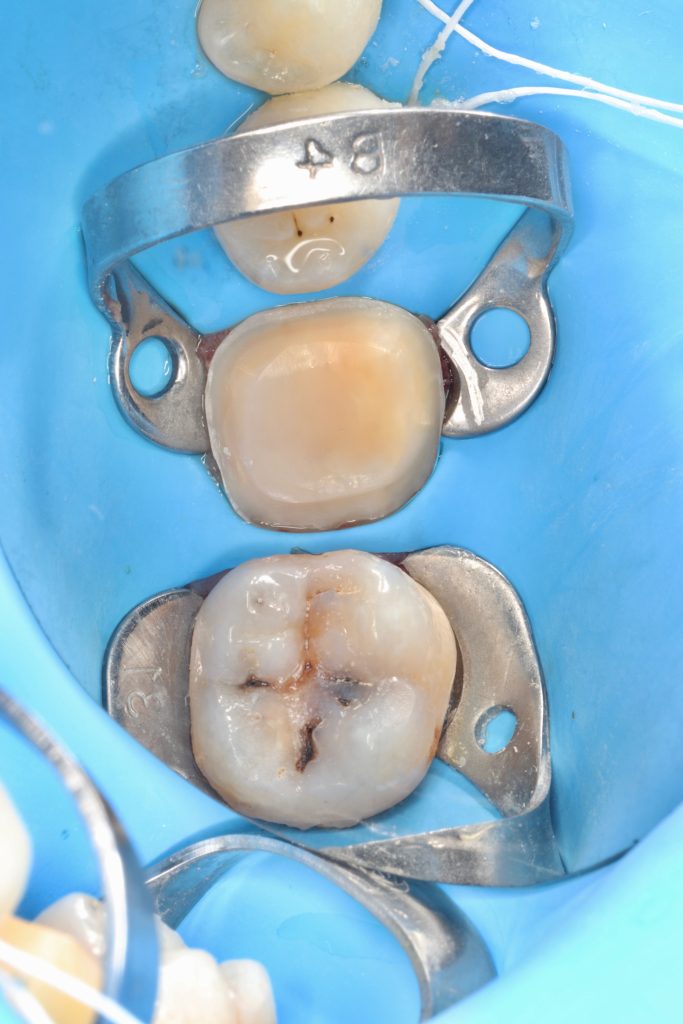

3.6 in-direct resin ceramic

3.7 direct composite

3.6 is not recommended for direct restoration due to the thickness of the cusps.

The patient did not experience any spontaneous pain in the mandibular first molar cavity